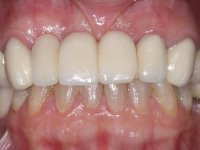

A paciente não gostava do seu sorriso, dizia que tinha “os dentes com um aspeto muito artificial”.

Perante a situação clínica apresentada, foi proposta uma reabilitação oral que melhorasse a aparência estética, mas que também solucionasse a falta de dentes posterior, procurando uma reabilitação funcional e estética. Foi proposta a substituição da ponte metalo-cerâmica por uma ponte com infraestrutura em zircónio, revestida a cerâmica coronária e gengival. A zona edêntula do primeiro quadrante seria reabilitada com 2 implantes e uma ponte de dois elementos. Pretendia-se com este plano de tratamento recuperar a dimensão vertical da oclusão e reformular a anatomia dentária, criando uma aparência estética mais natural.

Foram realizadas impressões em alginato a ambas as arcadas, acompanhadas pelo registo das relações inter-maxilares e recolha de informação com arco facial. No laboratório foi confecionada uma ponte provisória de 13 elementos em acrílico autopolimerizável na qual foi incorporado um reforço metálico. Os dentes 1.7/1.4/1.3/2.2/2.3/2.4 e 2.6 foram utilizados como pilares. A ponte metalo-cerâmica foi removida após a realização de cortes longitudinais feitos com brocas diamantadas. Os preparos dentários foram re-preparados e a ponte provisória foi rebasada em boca com acrílico auto-polimerizável. Após a confeção da ponte provisória, foi confecionada uma epítese gengival em resina composta com tonalidade gengival, com o objetivo de funcionar como uma maquete, que permitisse à paciente pré visualizar a possibilidade de utilização de cerâmica de tonalidade gengival no trabalho final. Esta opção foi aprovada como válida pela paciente. Posteriormente foi planeada e executada a colocação de dois implantes no primeiro quadrante. O monobloco provisório foi retirado para a colocação dos implantes e após a cirurgia foi novamente cimentado provisoriamente. Passado o período de osteointegração foram realizadas as impressões ao maxilar superior. Na zona anterior foram utilizados fios de afastamento gengival impregnados e nas zonas posteriores foi utilizada pasta de caolino. A impressão aos implantes utilizou a técnica de moldeira aberta. O material de impressão utilizado foi o silicone de adição putty soft e regular, ambos de presa rápida. No laboratório, o modelo das restaurações provisórias e a maquete em resina serviram de orientação ao enceramento da infra-estrutura. O modelo de trabalho em gesso e o enceramento da infraestrutura foram colocados num scanner laboratorial e deram origem a um modelo de trabalho digital no qual foi sobreposta a digitalização da infraestrutura encerada. Esta sobreposição facilitou o desenho CAD da infraestrutura em Zr. Posteriormente, o desenho CAD por um processo CAM de fresagem deu origem às peças de Zr. A infraestrutura foi pigmentada com uma coloração rosada, que favorecesse a colocação posterior de cerâmica de tonalidade gengival. Durante a modelação da infraestrutura foi detetada a necessidade de aumentar o desgaste oclusal no dente 1.4. Este desgaste foi feito no modelo de trabalho real e foi confecionada uma guia de controlo de desgaste em acrílico que acompanhou a prova das infraestruturas. Em boca foi realizado o desgaste corretivo e foi realizada a prova das peças de Zr. Durante a prova foi reavaliada a escolha da cor da cerâmica de tonalidade gengival. O tratamento foi finalizado no laboratório e após aprovação pela paciente foi colocado definitivamente em boca.